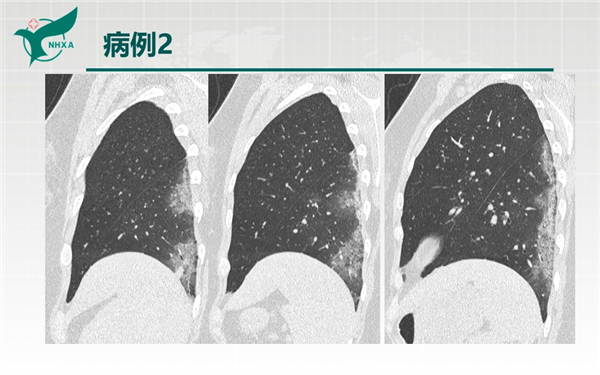

【病例分享】新型冠狀病毒肺炎3例(西安市第九醫(yī)院)

幻燈片10.jpg